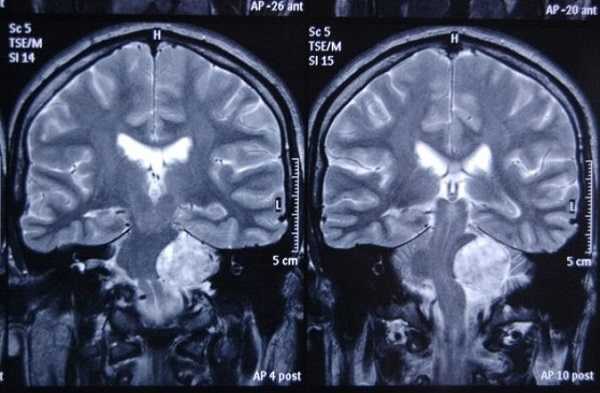

Липома ММУ (указана стрелками) на снимке МРТ головного мозга в аксиальной проекции